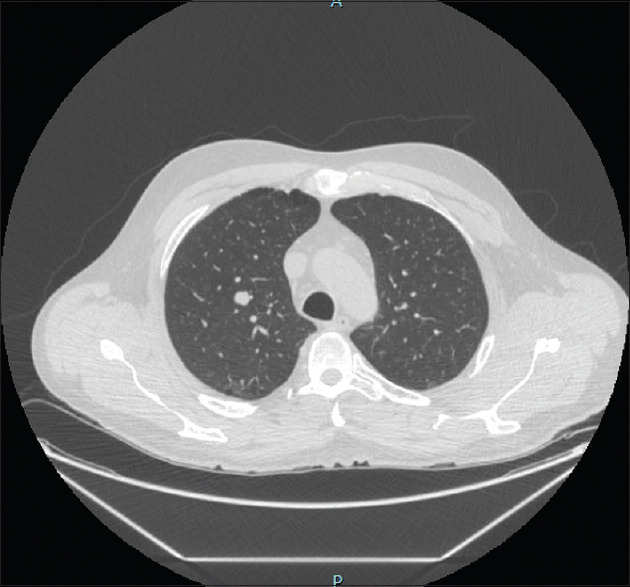

摘要错构瘤是一种常见的肺良性肿瘤。虽然大多数肺错构瘤位于肺实质内,但很少表现为支气管内肿瘤。我们描述了一例75岁的男性通过传统的柔性支气管镜切除支气管内错构瘤,另一例55岁的男性通过机器人导航支气管镜诊断支气管内错构瘤。我们还描述了过去13年中在我们机构诊断的支气管内错构瘤的其他三个病例的显著特征。随着先进的导航支气管镜技术的出现,我们预测支气管内错构瘤的鉴别率将会增加。

Abstract: Hamartoma is a common benign tumour of the lung. Although most pulmonary hamartomas are located within the lung parenchyma, rarely they present as endobronchial tumours. We are describing one case of a 75-year-old gentleman with endobronchial hamartoma removed via traditional flexible bronchoscopy and another case of a 55-year-old gentleman whose endobronchial hamartoma was diagnosed via robotic navigational bronchoscopy. We are also describing the salient features of three other cases of endobronchial hamartoma diagnosed at our institution in the last 13 years. With the emergence of advanced navigational bronchoscopy techniques, we predict that the incidence of identifying endobronchial hamartomas will increase.